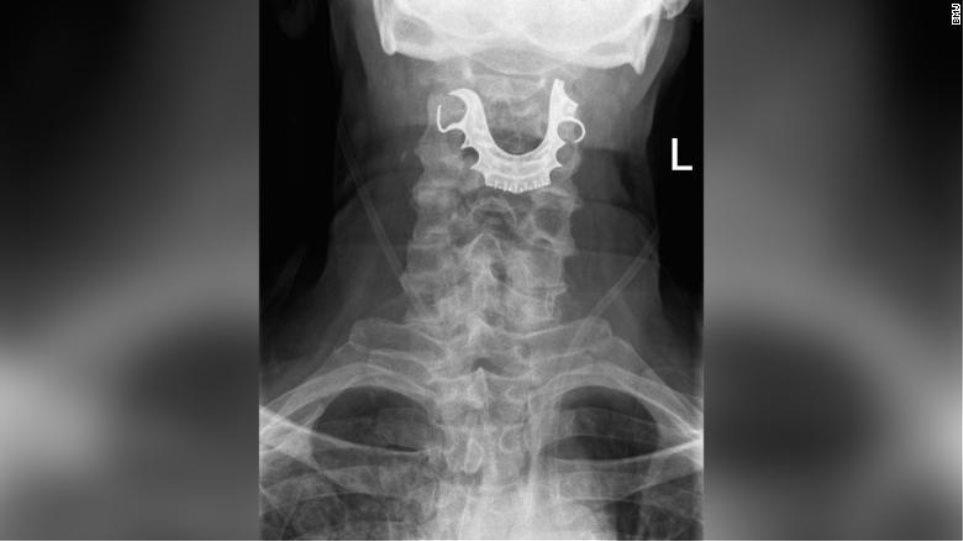

ΔΙΕΘΝΗΗ μασέλα του έφυγε από τη θέση της κατά τη διάρκεια χειρουργικής επέμβασης